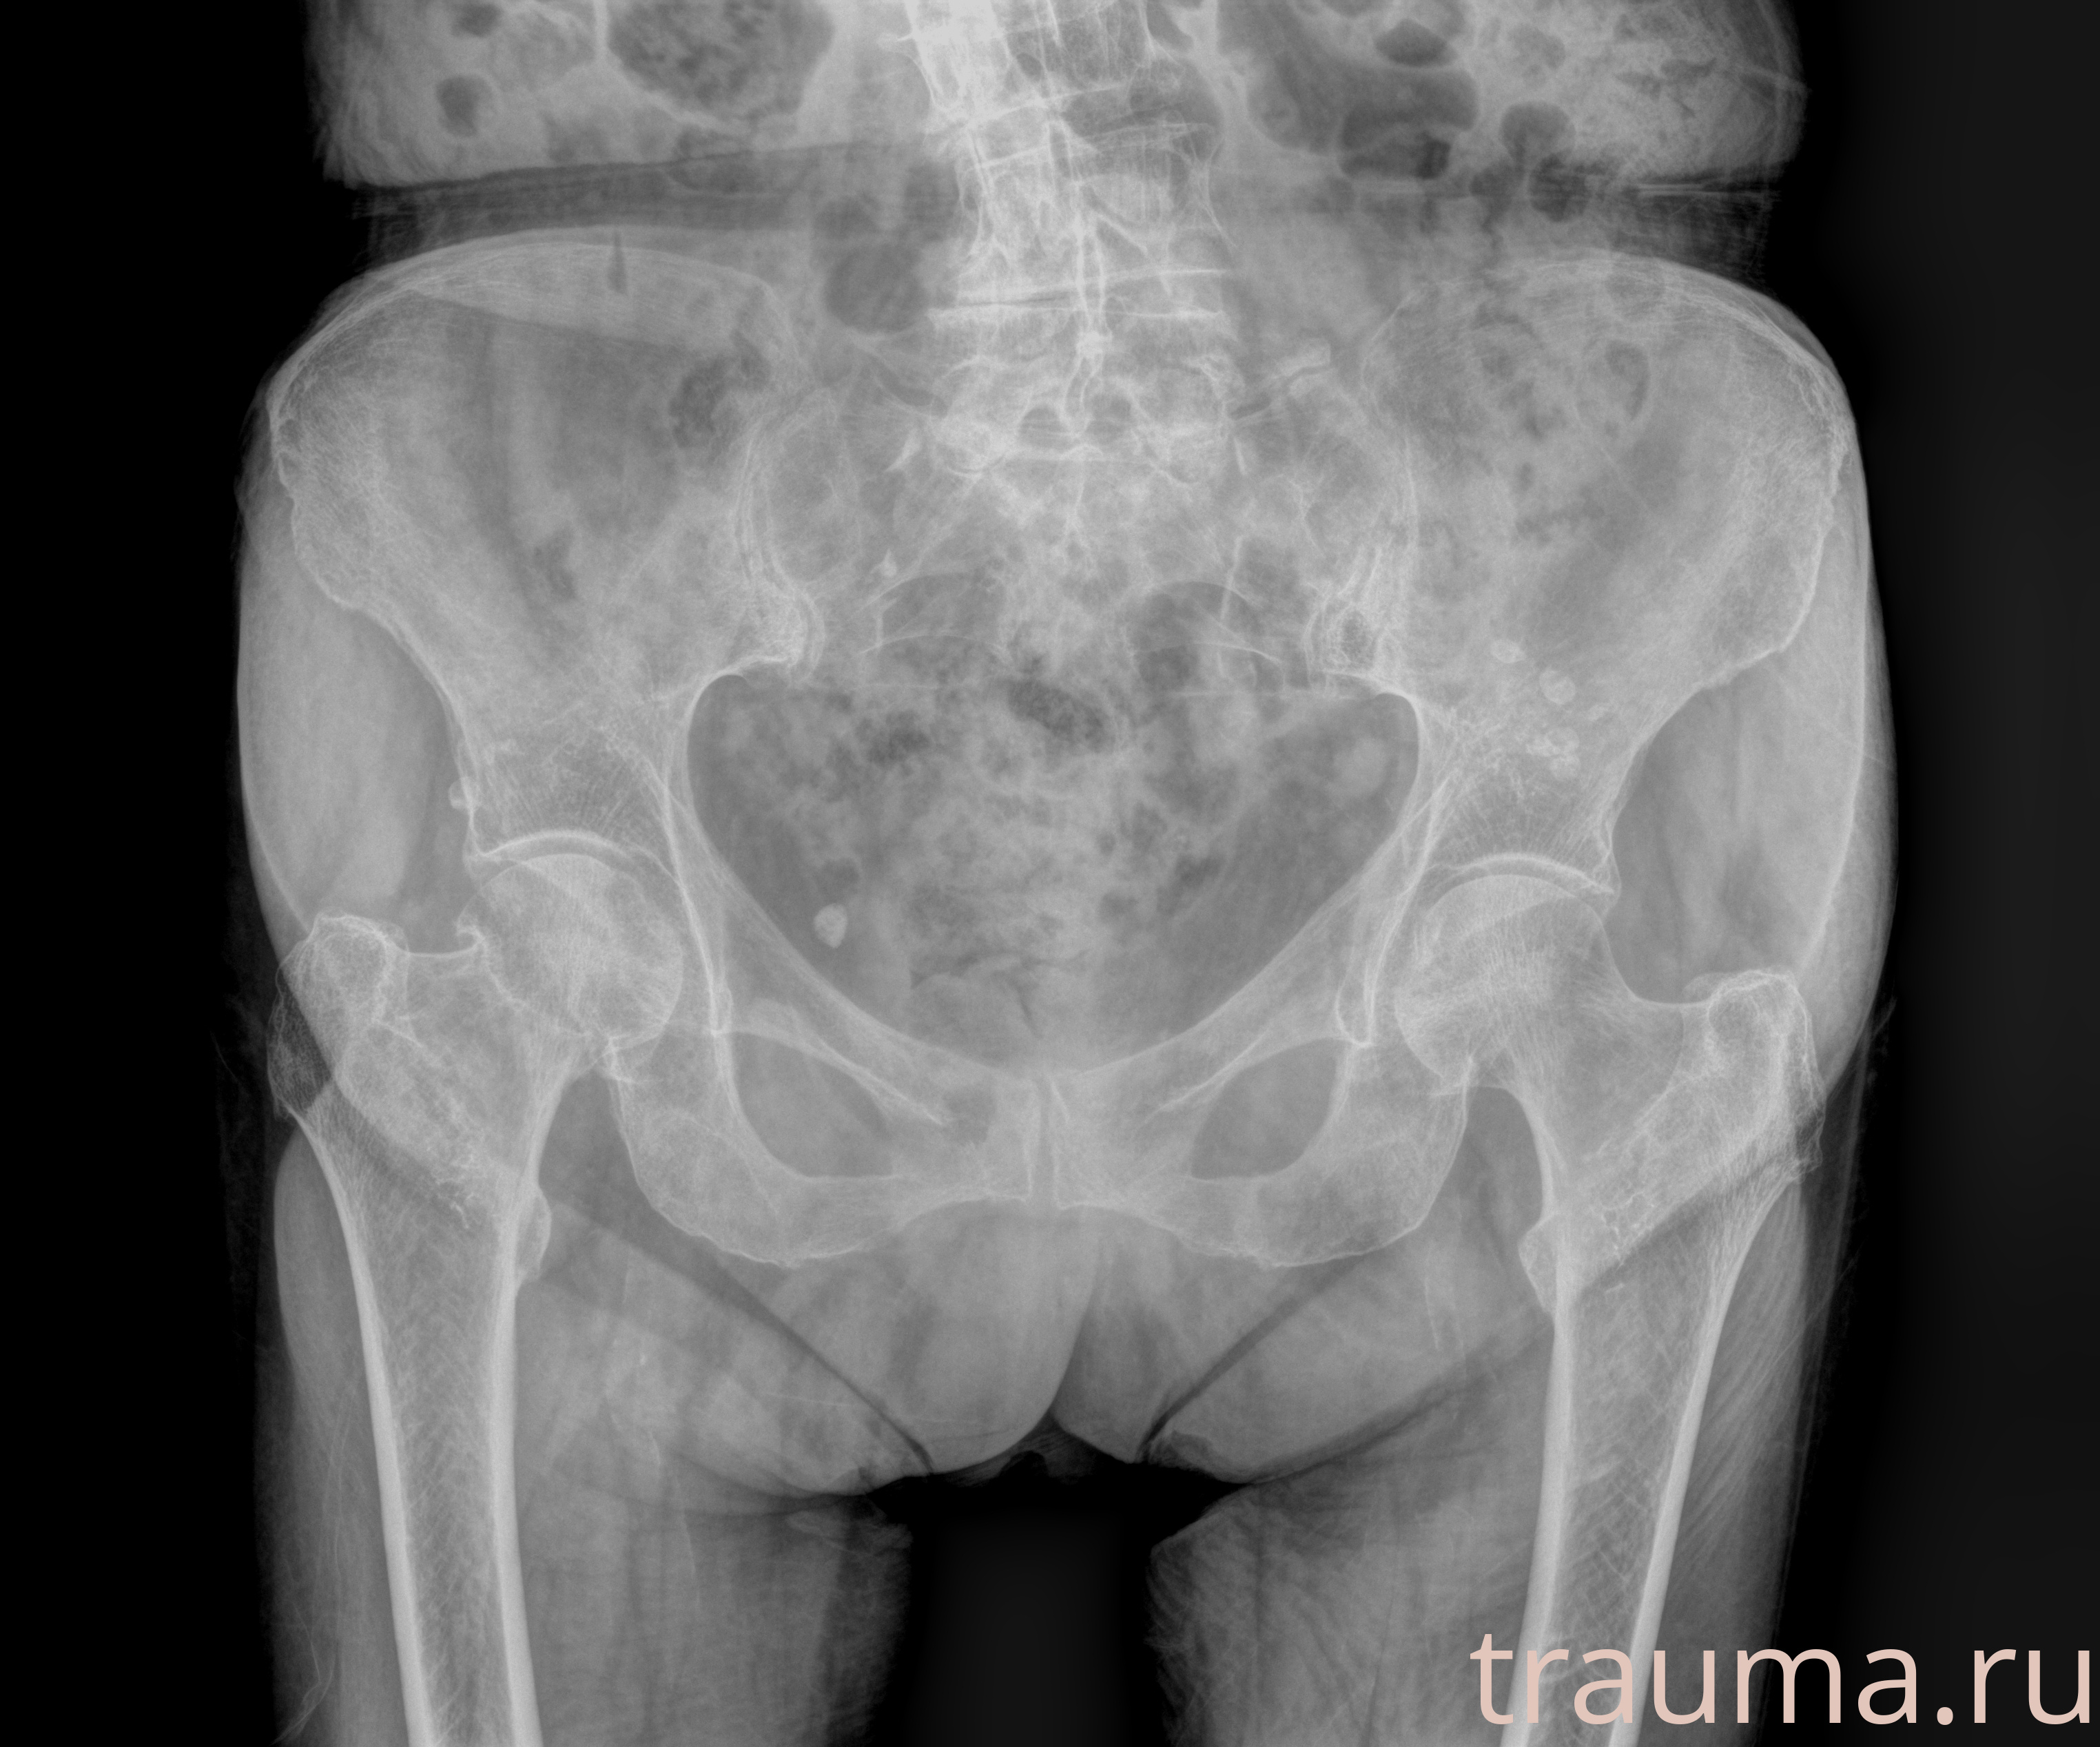

Рентген на дому: по вашему адресу приезжает врач-рентгенолог, травматолог-ортопед с мобильным рентгеновским аппаратом, проводит диагностику травмы или заболевания, делает необходимые рентгенограммы, дает рекомендации по дальнейшему лечению. Получить качественные снимки в домашних условиях возможно благодаря уникальной методике, разработанной МосРентген Центром для института  Склифосовского